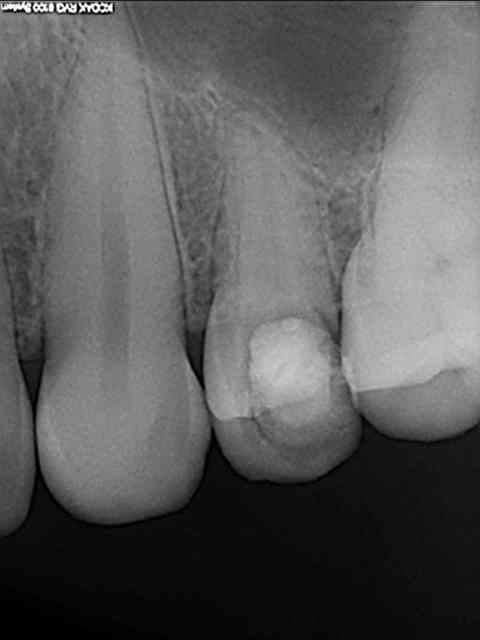

ne jamais faire une jolie provisoire

comme ça la prothèse conventionelle est zolie...

mis à part le liseret gris du collet suis content du résultat et pourtant c'était pas gagné d'avance : pas de GA ou peu et nécessité de faire une rog

donc la EII et ROG (nanobone + collagene +prf)

pas de MCI

à la réouverture déplacement en vestibulaire de la GA palatine pour redonner du "volume"

fouilla content il en faut peu pour être heureux..